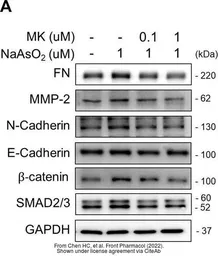

The data was published in the 2022 in Front Pharmacol. PMID: 35517780

The data was published in the 2022 in Front Pharmacol. PMID: 35517780

The data was published in the 2022 in Front Pharmacol. PMID: 35517780